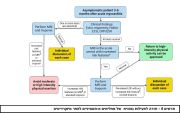

| 06:08, 31 באוקטובר 2023 | Myocarditis3.jpg (קובץ) |  |

130 קילו־בייטים | Motyk | 1 | |

| 14:51, 30 באוקטובר 2023 | Myocarditis2.png (קובץ) |  |

64 קילו־בייטים | Motyk | 1 | |

| 13:08, 30 באוקטובר 2023 | Myocarditis1.png (קובץ) |  |

235 קילו־בייטים | Motyk | 1 | |

| 12:06, 30 באוקטובר 2023 | Myocarditis4.jpg (קובץ) |  |

142 קילו־בייטים | Motyk | 1 | |